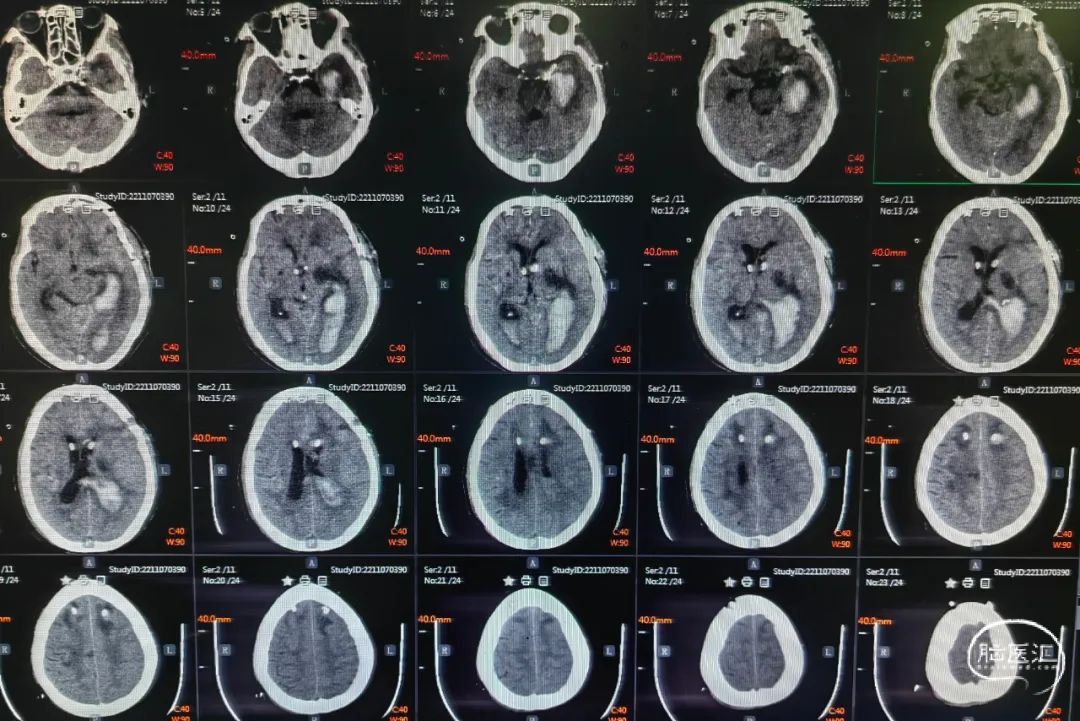

术前头颅CT提示:左侧基底节区脑出血破入脑室系统。

术后一周头颅CT提示:脑室系统积血较前明显减少。

卧床一周胸部CT:双肺片状炎症。